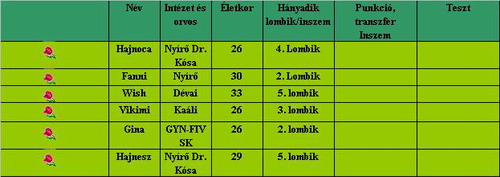

Hajnoca

Eletjelrol jut eszembe, Hajnesz veled mi van?